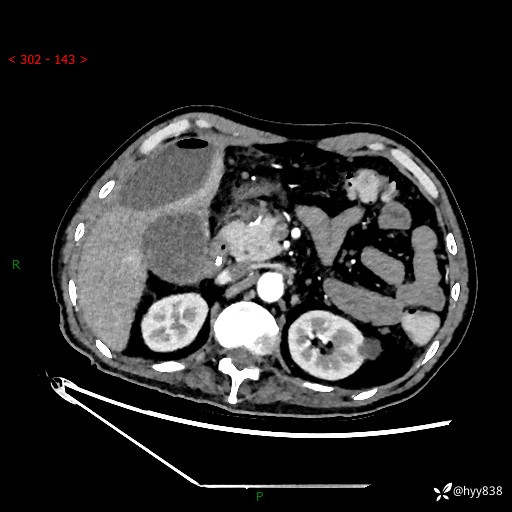

腹部CT平扫

增强